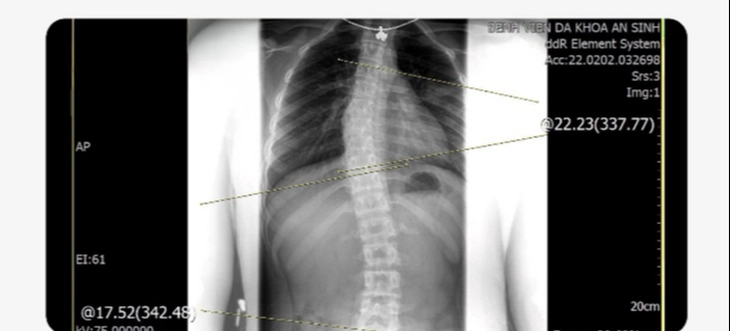

Một hình ảnh cho thấy cột sống bị cong vẹo